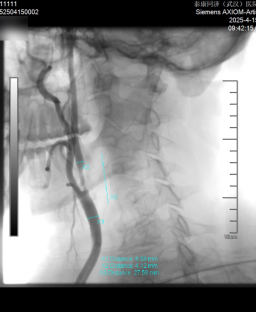

近日,張庭保教授團(tuán)隊(duì)為患者實(shí)施“右側(cè)頸內(nèi)動(dòng)脈球囊擴(kuò)張術(shù)+支架植入術(shù)+左側(cè)椎動(dòng)脈藥物球囊支架置入術(shù)”。術(shù)后腦血管造影顯示,右側(cè)頸內(nèi)動(dòng)脈及左椎動(dòng)脈狹窄情況明顯改善?;颊咝g(shù)后恢復(fù)良好,目前已康復(fù)出院。